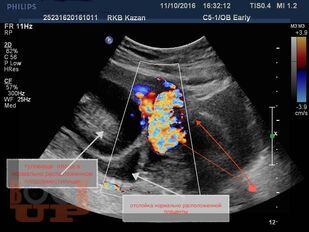

В методических рекомендациях приведен сравнительный анализ существующих методов лечения беременности в рубце на матке после кесарева сечения в нижнем сегменте. Подробно изложен собственный запатентованный протокол лечения рубцовой беременности в зависимости от данных ультразвукового исследования в совокупности с уровнем ХГЧ в сыворотке крови беременной, разработанный авторами. Данный протокол позволяет на основании полученных диагностических данных выбрать оптимальный метод органосохраняющего лечения, определить методы последующего контроля состояния пациента.